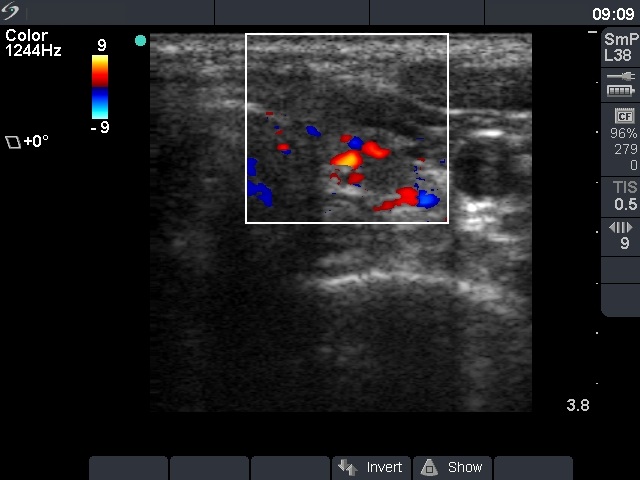

Ultrasonography: the thyroid was minimally hypoechogenic. There was a small hypoechogenic lesion in the left lobe with the dimensions of 8x7x8 mm.